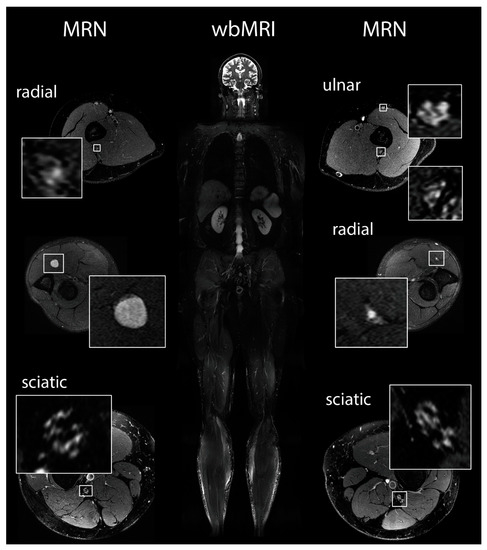

2.5. Magnetic Resonance Imaging and Magnetic Resonance Neurography

3.6. Magnetic Resonance Imaging and Neurography

- (1)

- Manifest peripheral nerve tumors of more than 5mm in diameter;

- (2)

- Intermediate-sized nerve nodules, defined as neural caliber increase between 2 and 5 mm in diameter; and

- (3)